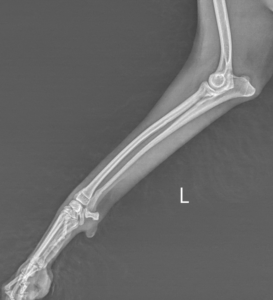

主な検査はレントゲン検査です。骨折部位や骨片のズレ、粉砕の程度を評価します。必要に応じて以下の検査が行われます。

・複数方向からのレントゲン

骨折の治療方法

・外固定(ギプス、包帯)

・内固定(プレート、ピン、スクリュー)

・創外固定

軽度の骨折では外固定のみで治癒することもありますが、多くの場合、安定した治癒を目指して手術が選択されます。